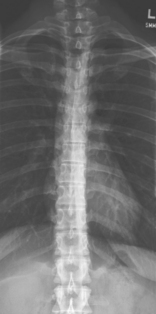

• 35 × 43 cm L.W. (14 × 17″) or 35 × 92 cm (14 × 36″)

• Compensating filters to produce a more uniform density of spine

Erect, standing or seated, spine aligned and centered to centerline, arms at side, no rotation of pelvis or thorax